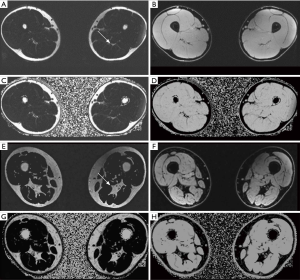

CT allows for the attenuation-based depiction of body compartments with high resolution. Besides, it facilitates the segmentation of muscle cross-sectional areas per slice as well as for 3D volume segmentation, e.g., calculation of total muscle mass. As attenuation data are scaled in relation to water (HU 0) and thus comparable among different scanners, a threshold-based approach is applied, typically at a range of around −30 to 150 Hounsfield Units (HU) as segmentation mask (12,13). Unlike DEXA, muscle segmentation also allows for macroscopic morphologic assessment of muscle quality. Within the segmented muscle cross-sectional areas, myosteatosis is identified by streaks of negative HU values and fatty infiltration lowers muscle attenuation as fat voxels by definition have negative HU values (13). However, muscle and fat volume segmentation is time-consuming, which is why CT currently focusses on muscle quantity assessment extrapolated from a single slice, most commonly at the level of the third or fourth lumbar vertebra (13). There is large-scale research that has recently been investigating the automation of muscle areas in CT, enhancing its diagnostic yield in terms of whole-body muscle volume assessment. As for other radiological demands, automation enhanced by artificial intelligence algorithms has already demonstrated the potential for muscle mass segmentation (14). However, the use of CT for this task is naturally associated with substantial radiation dose and therefore usually limited to a specific population and indication, limiting its role for longitudinal observations (5,15).